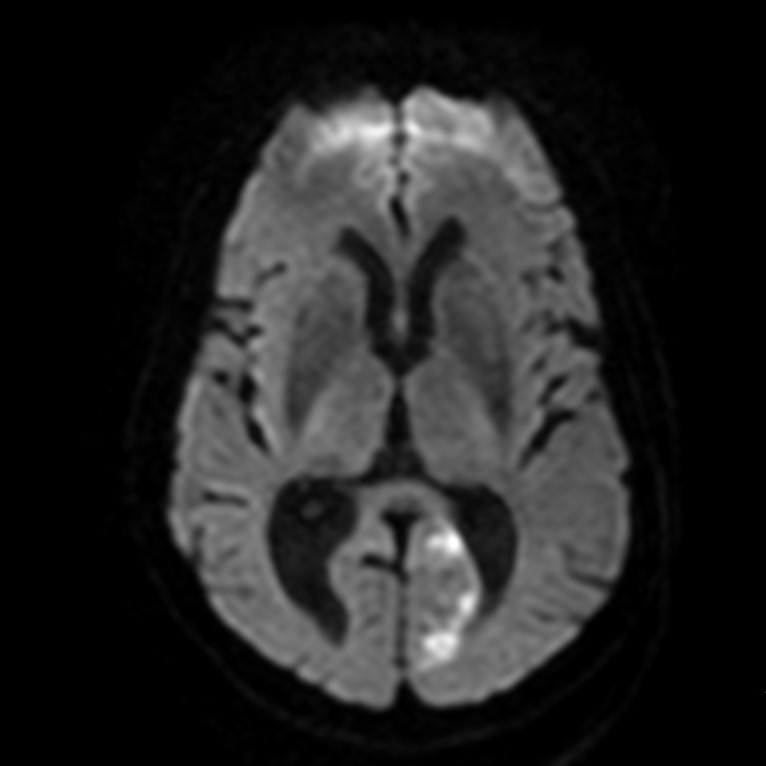

Существует определенный протокол МРТ диагностики при инсульте, включающий в себя 4 вида МР исследований в течении 24 часов. Так, особый интерес представляет DWI – диффузно взвешенная МРТ, которая делается через 3 часа после предполагаемого острого периода. Так как на DWI будут видны отечные структуры головного мозга, что очень важно в комплексной МР диагностике. DWI улавливает микро-движения молекул воды через клеточные мембраны.